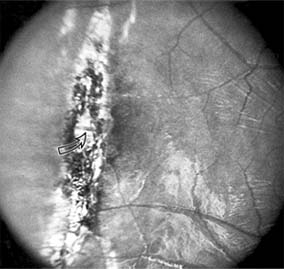

Figure 10-13

Figure 10-13: Traumatic choroidal rupture resulting in pigmented scar. A choroidal vessel (arrow) is visible through the scar.

Blunt trauma to the anterior segment of the eye may cause a contrecoup injury to the retina called commotio retinae. The retina develops a gray-white color that affects primarily the outer retina and may be confined to the macular area (Berlin's edema) or may involve extensive areas of the peripheral retina. The retinal whitening in the macular area may clear completely, or impairment of central vision may be permanent and associated with a pigmented retinal scar (Figure 10-13) or a macular hole. Trauma similar to that which causes Berlin's edema may also cause choroidal rupture with subretinal hemorrhage and permanent central vision loss.